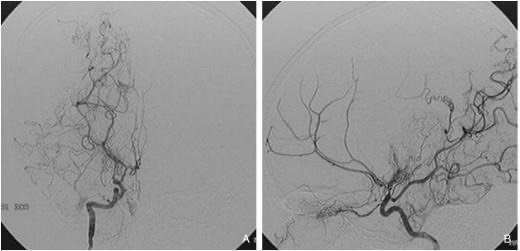

수술치료(뇌혈류 재건술, Revascularization surgery)

모야모야병의 핵심 치료는 뇌혈류 공급을 위한 새로운 통로를 만들어주는 수술입니다.

① 직접 우회술(Direct bypass)

• 측두동맥(STA)을 직접 뇌혈관(MCA)과 연결해 혈류를 즉시 공급하는 방식 • 성인에서 가장 많이 시행

• 수술 직후부터 혈류 개선 효과가 빠르게 나타납니다.

② 간접 우회술(Indirect bypass)

• 근육이나 막 조직을 뇌 표면에 붙여 그 조직에서 자라는 새로운 혈관이 뇌를 공급하도록 유도 • 소아에서 많이 사용

• 혈류 증가 효과가 나타나기까지 수개월이 필요합니다.

③ 혼합 우회술(Combined bypass)

• 직접 + 간접 방법을 동시에 시행하는 방식

• 빠른 효과 + 장기 안정성을 동시에 노릴 수 있는 방법입니다.